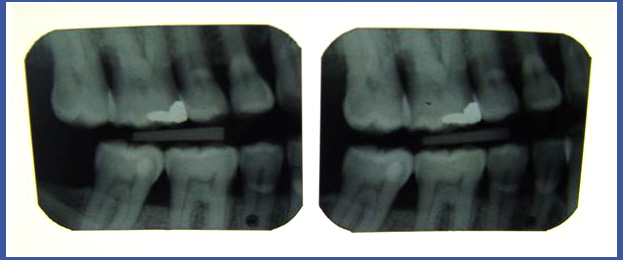

1.צילומי נשך:

בדרך כלל נעשים במרפאת שיניים – זהו הצילום המראה את החלק הכותרתי של השיניים הטוחנות והמלתעות בשתי הלסתות באותו צילום (במקרים רבים,יספיקו לרופא שני צילומים קטנים המבוצעים במקום), הצילום מאפשר לנו לראות נגעי עששת בחלק בין השניים ועל גבי משטחי הלעיסה של השיניים! בדרך כלל צילום נעשה בבדיקה שיגרתית אצל מתרפאים ללא בעיות של נסיגת עצם וחניכיים וללא כתרים על השיניים! בשיניים שיש עליהם כתרים, צילום נשך לא יספיק לצורך האבחנה ולכן יש לעשות צילום מסוג אחר.